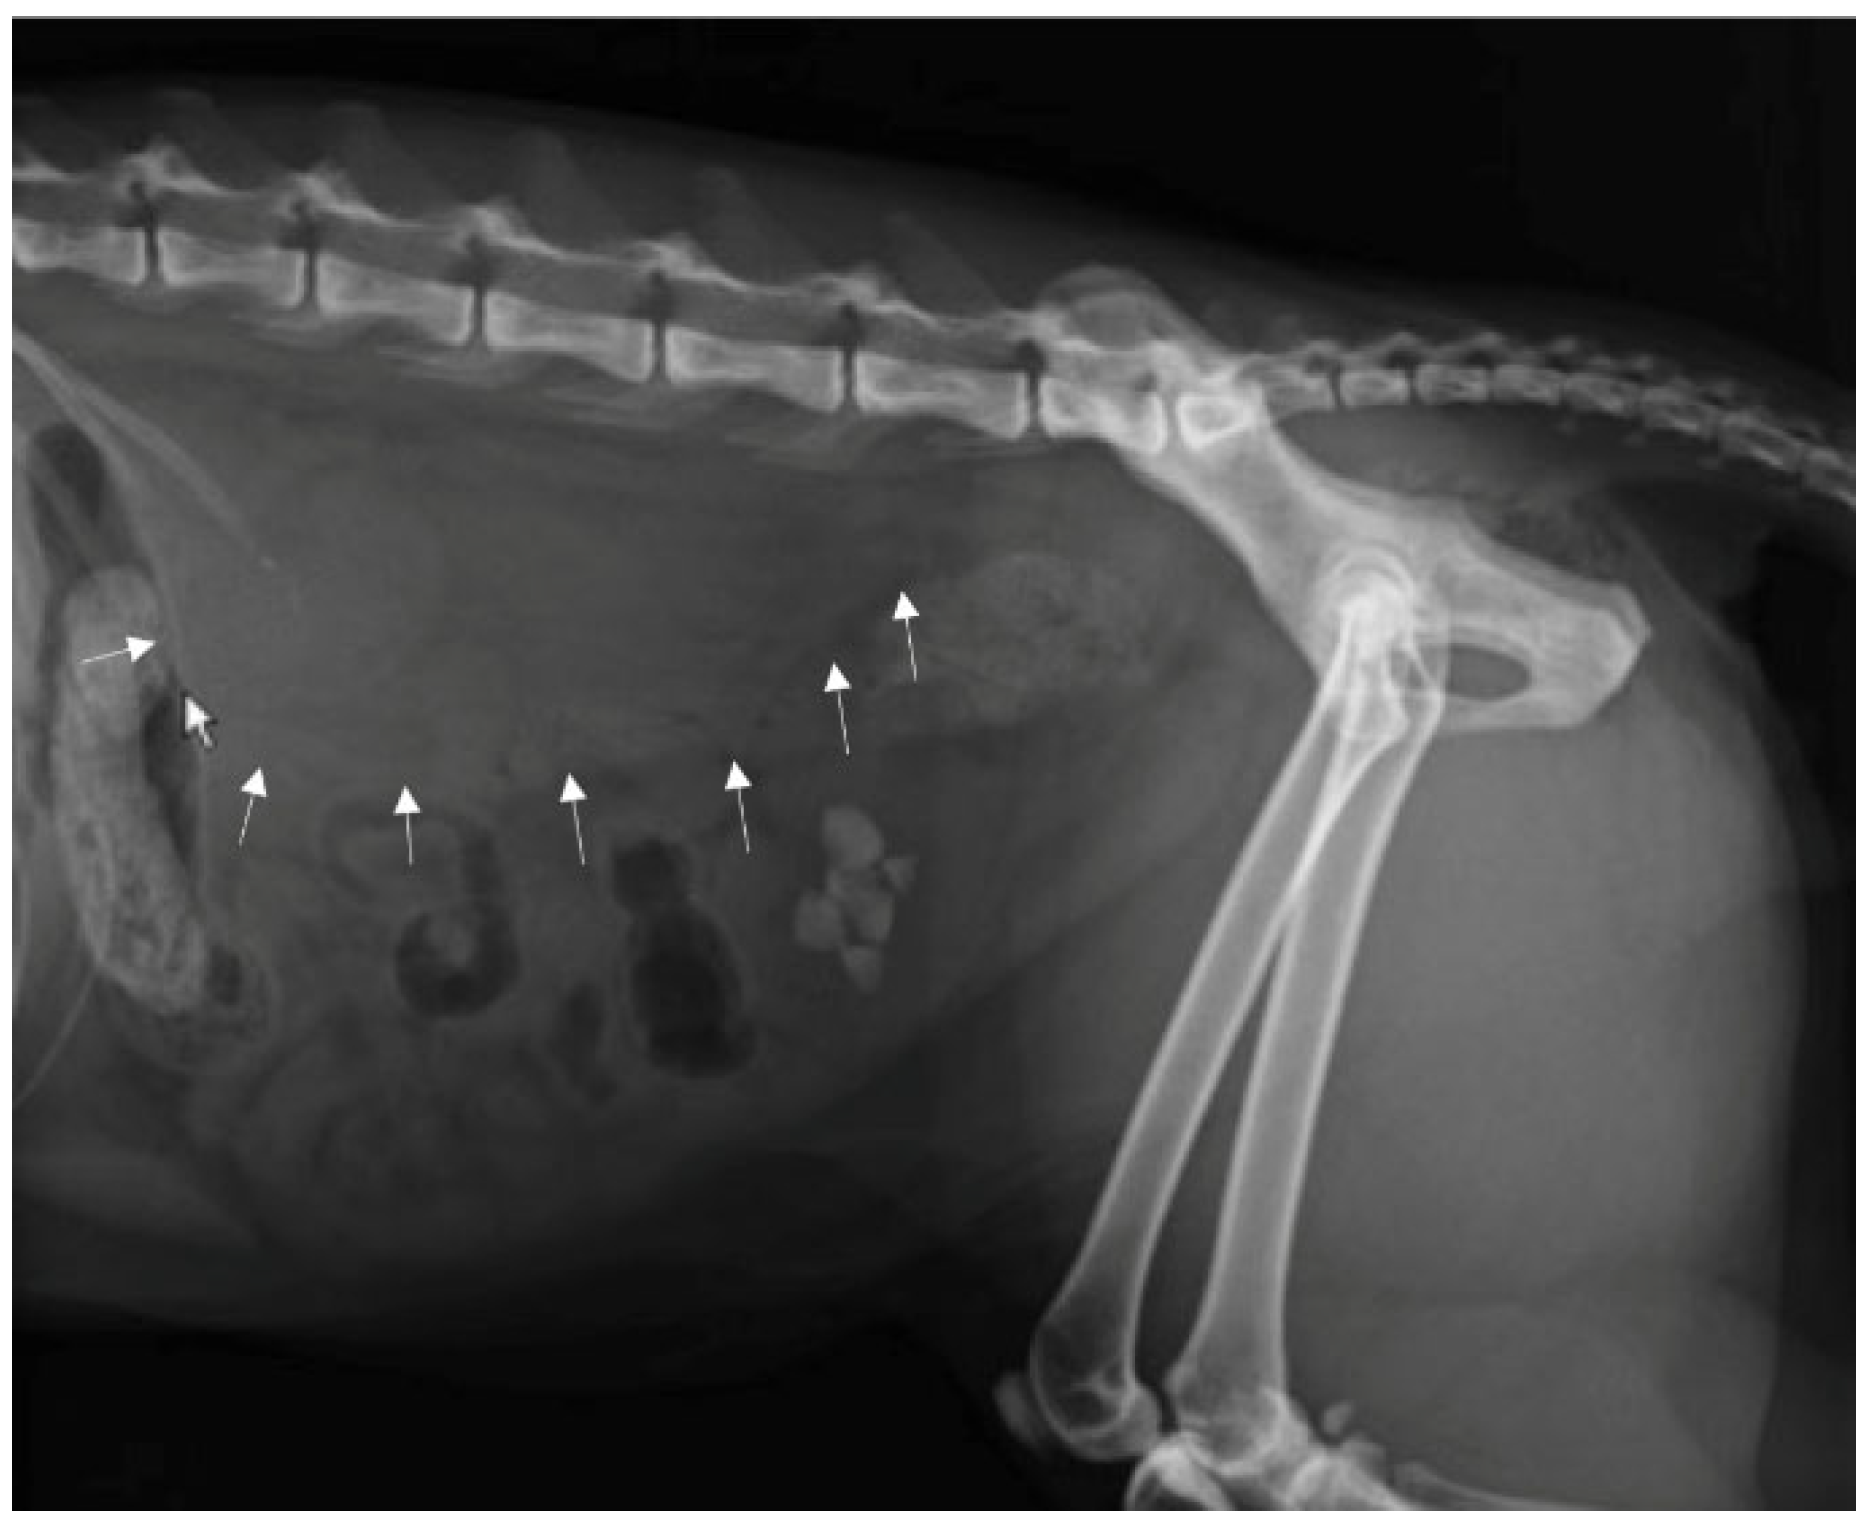

Positive contrast radiographs in the lateral and ventrodorsal projections immediately after the injection of the contrast agent allowed for defining the extent of the lesion, outlining the fluid collection as a large well-marginated homogeneous radiopaque area in the left retroperitoneal space and differentiating it from ascite (Figure 5A,B).

Figure 5.

Positive contrast X-ray exam of the abdomen: (A) Left lateral and (B) ventrodorsal projections. Contrast medium that borders the fluid collection is shown in arrows.